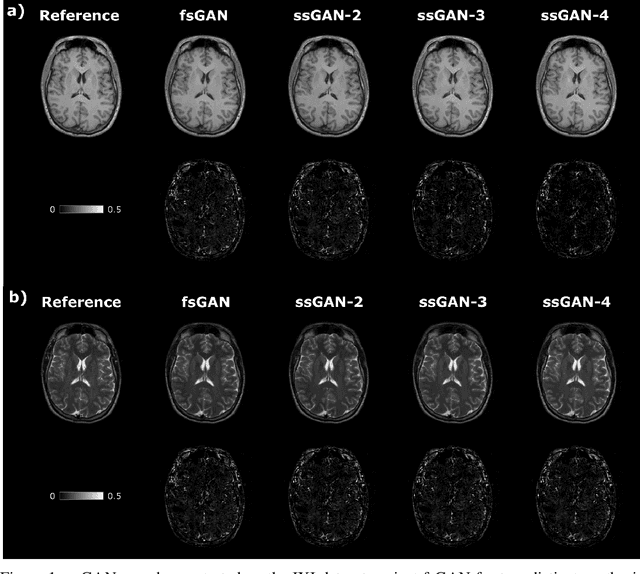

Abstract:This study proposes a novel semi-supervised learning framework for mutually accelerated multi-contrast MRI synthesis that recovers high-quality images without demanding large training sets of costly fully-sampled source or ground-truth target images. The proposed method presents a selective loss function expressed only on a subset of the acquired k-space coefficients and further leverages randomized sampling patterns across training subjects to effectively learn relationships among acquired and nonacquired k-space coefficients at all locations. Comprehensive experiments performed on multi-contrast brain images clearly demonstrate that the proposed method maintains equivalent performance to the gold-standard method based on fully-supervised training while alleviating undesirable reliance of the current synthesis methods on large-scale fully-sampled MRI acquisitions.